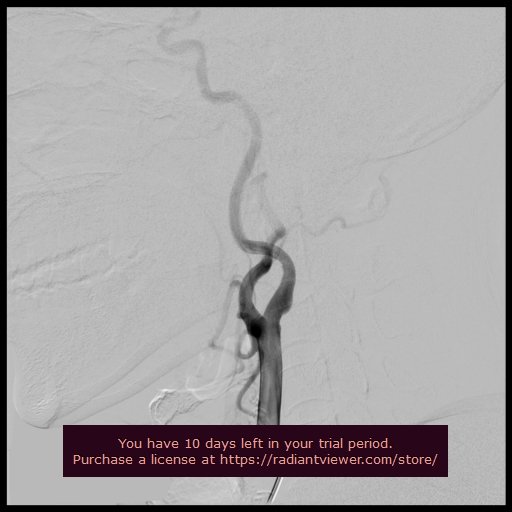

NECK ANGIOGRAPHY